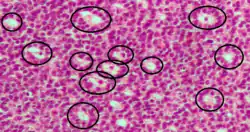

Cuerpos de Call-Exner

Los cuerpos de Call–Exner, con un aspecto parecido al del folículo, es una pequeña perforación entre las células de la granulosa relleno de un fluido eosinofílico.[1] Las células de la granulosa están generalmente organizadas aleatoriamente alrededor del espacio.

Son patognomónicos de tumores de células de la granulosa.

Están compuestos de secreciones de las células de la granulosa empaquetados en una membranas y tienen relaciones con la formación de líquido folicular los cuáles se observan estrechamente organizadas entre las células de la granulosa.